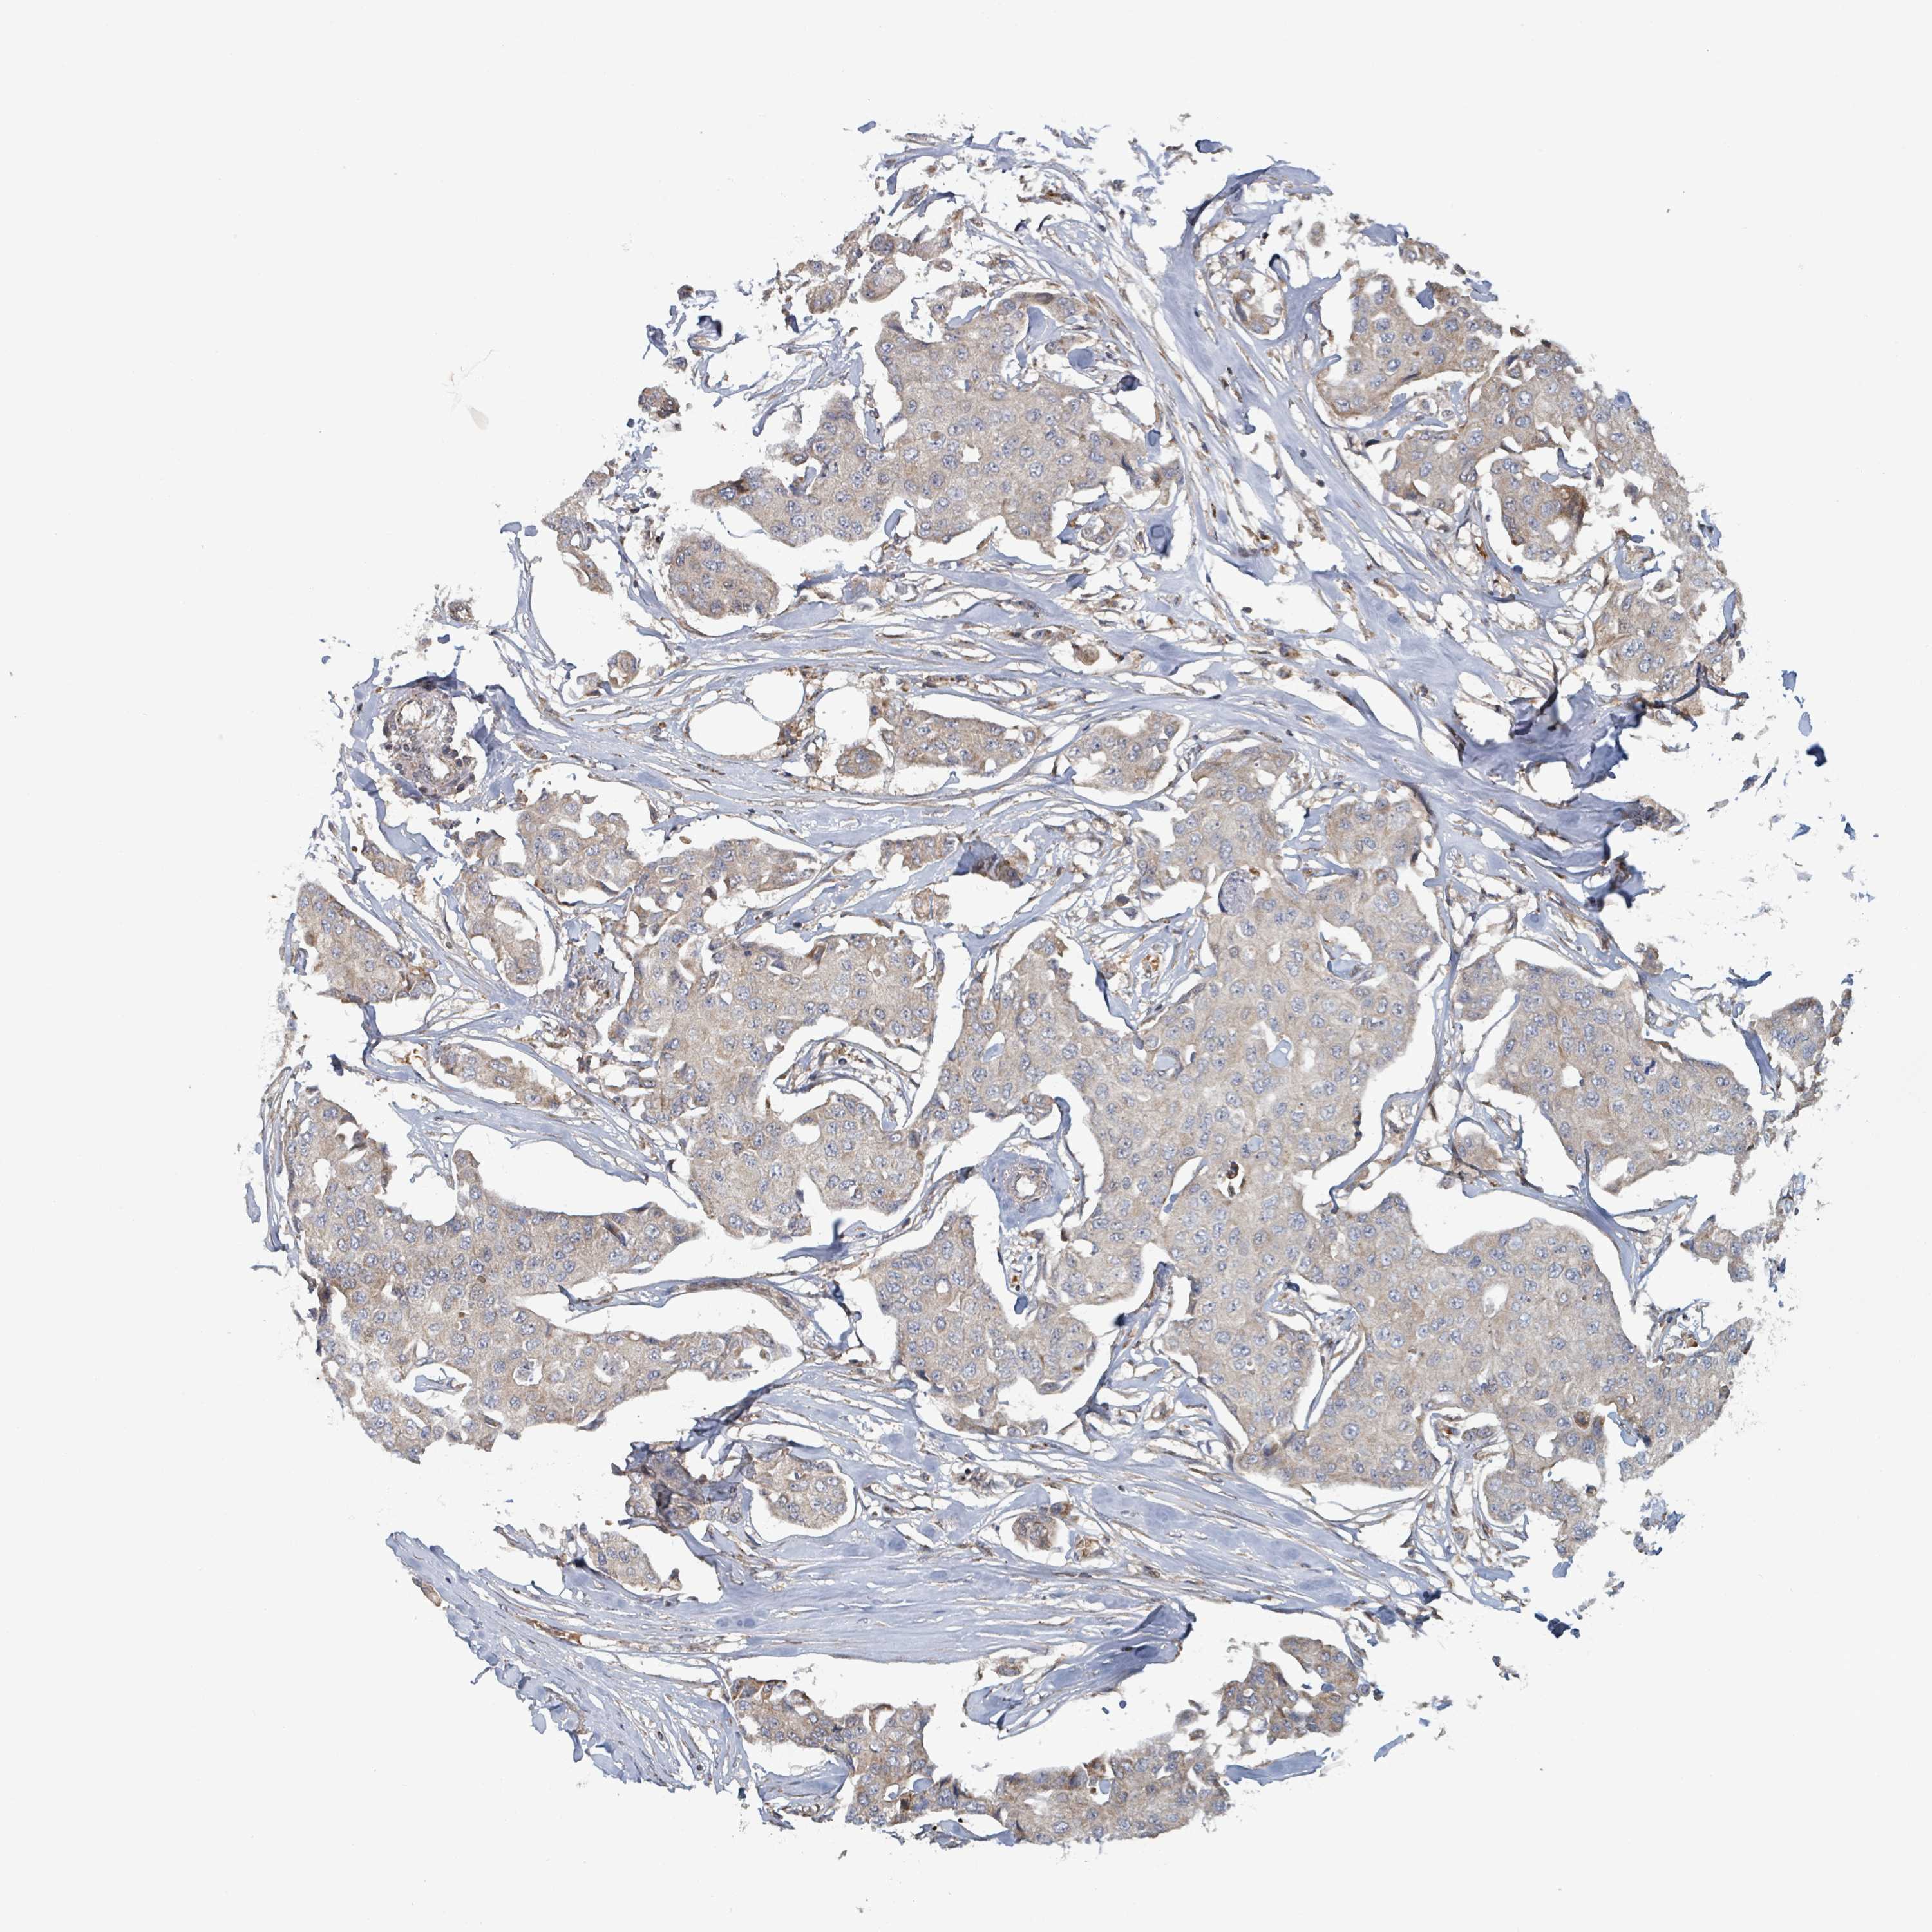

CANCER BREAST CANCER Show tissue menu

BRCA TCGA BRCA VALIDATION PROTEIN EXPRESSION

ANTIBODIES

AND

VALIDATION